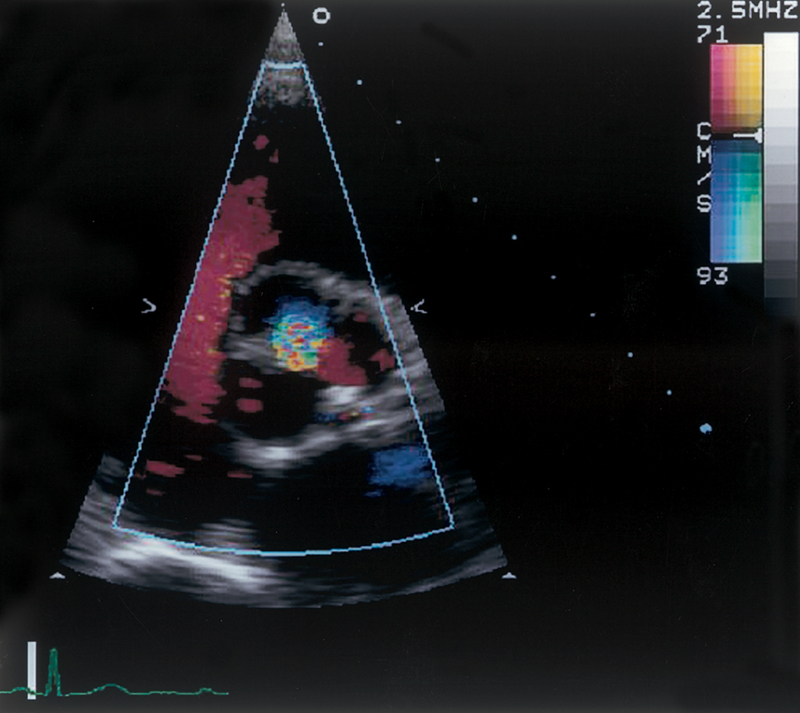

فحوصات تشخيصية لبعض امراض القلب والشرايين التاجية